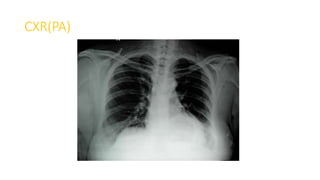

CXR(PA)

Upper GI Endoscopy

Barium Swallow

HRCT

Diagnosis

Left sided Bochdalek hernia with stomach herniating into left chest.

PLAN

Laparoscopic repair of Bochdalek hernia with reinforcement by dual mesh.

• Misdiagnosis of BH is common, as reported in this case, and may be

fatal

• Clinician should take great care during the management of patients

with persistent pulmonary symptoms and abnormal chest findings

• CT Scan are the only way to direct visualize the focal defect of

diaphragm, and also helps in establishes a definitive diagnosis

Conclusion

• BHs are uncommon clinical findings in adult population and cases

presenting with incarceration are even less common

• CT is preferred diagnostic tool for BHs

• Laparoscopic repair of an incarcerated BH is an excellent option

because of the advantages of its unique, minimally invasive nature